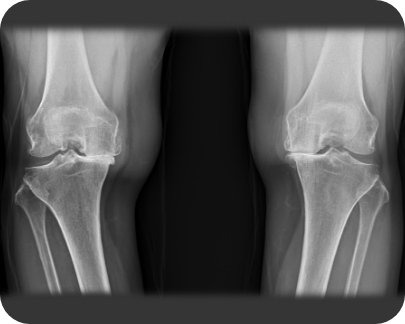

무릎인공관절 전치환술 사례1

• ▲ 수술 전

• ▲ 수술 후

무릎인공관절 전치환술 사례2